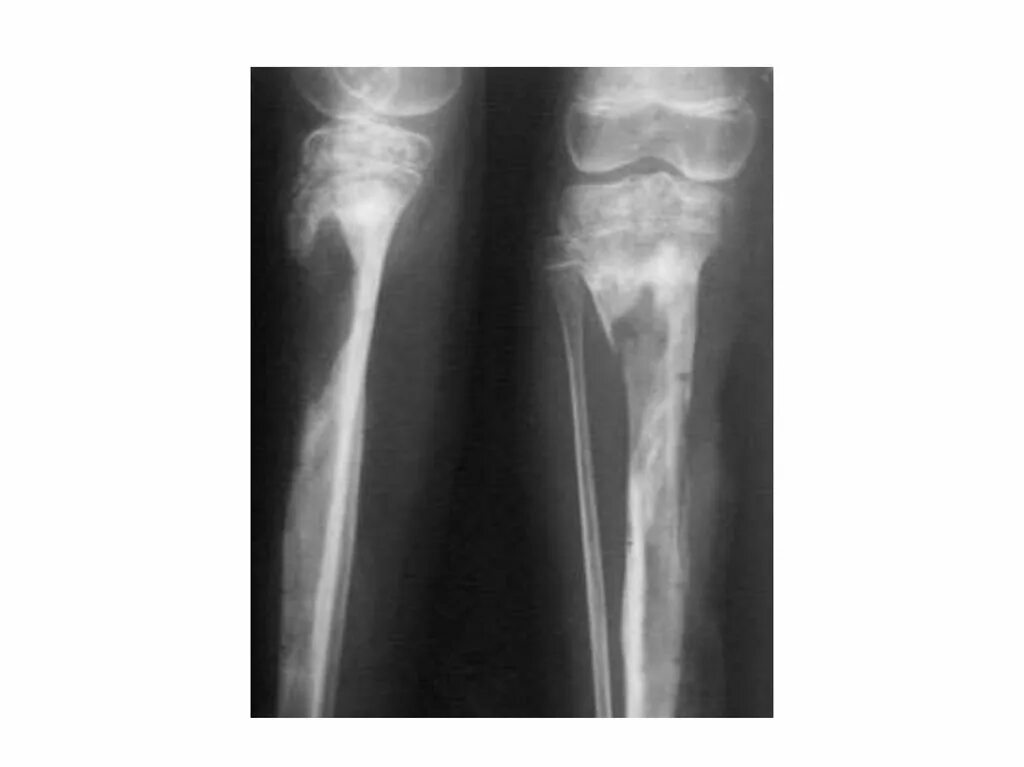

Зона деструкции